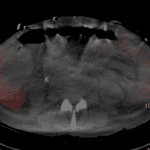

Age: 68

Sex: Male

Indication: Rule out postoperative bile leak, history of TIPS

Radiotracer: Tc99m Mebrofenin

Sample ReportPositive for biliary leak with bile collecting in the right sub-diaphragmatic region and in the right paracolic gutter.